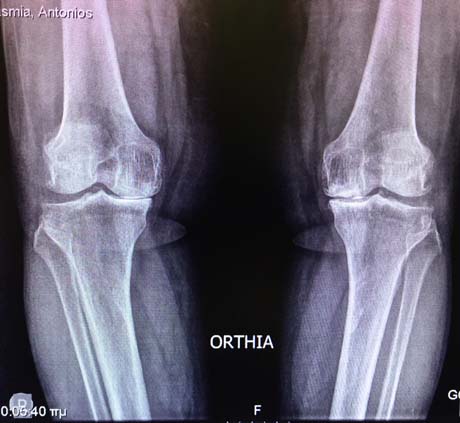

Προχωρημένη οστεοαρθρίτιδα άμφω των γονάτων.

Προεγχειρητικός ακτινολογικός έλεγχος αναδεικνείει τη σοβαρότητας της νόσου στα γόνατα του ασθενούς.